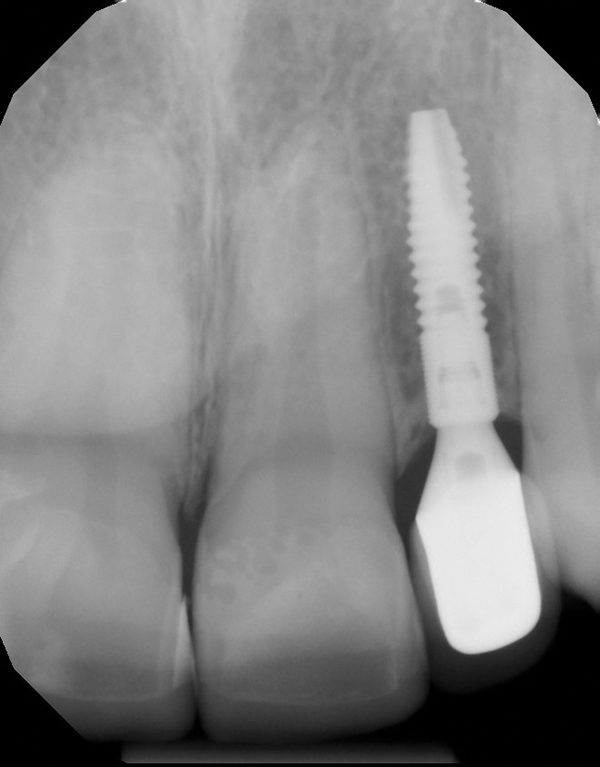

When the patient was 18 years old, an implant was placed in site No. 10 with no complications (Figure 9 and Figure 10). Three months later, a periapical radiograph was taken, the implant was torque tested, and a healing abutment (3 mm by 4 mm by 4 mm) was placed.

Fig 9 and Fig 10. An implant placed in site No. 10.